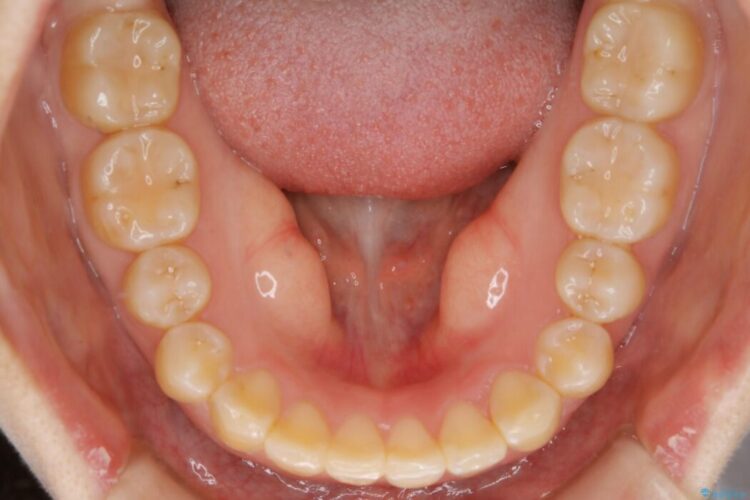

噛み合わせの違和感と前歯のガタガタを主訴に来院されました。

歯軸傾斜と軽度の叢生が見られましたので、通常の位置へと傾きを戻し少量の遠心移動に加えアーチ(歯列弓)の拡大とIPRを施すことで改善していく非抜歯での治療計画としました。